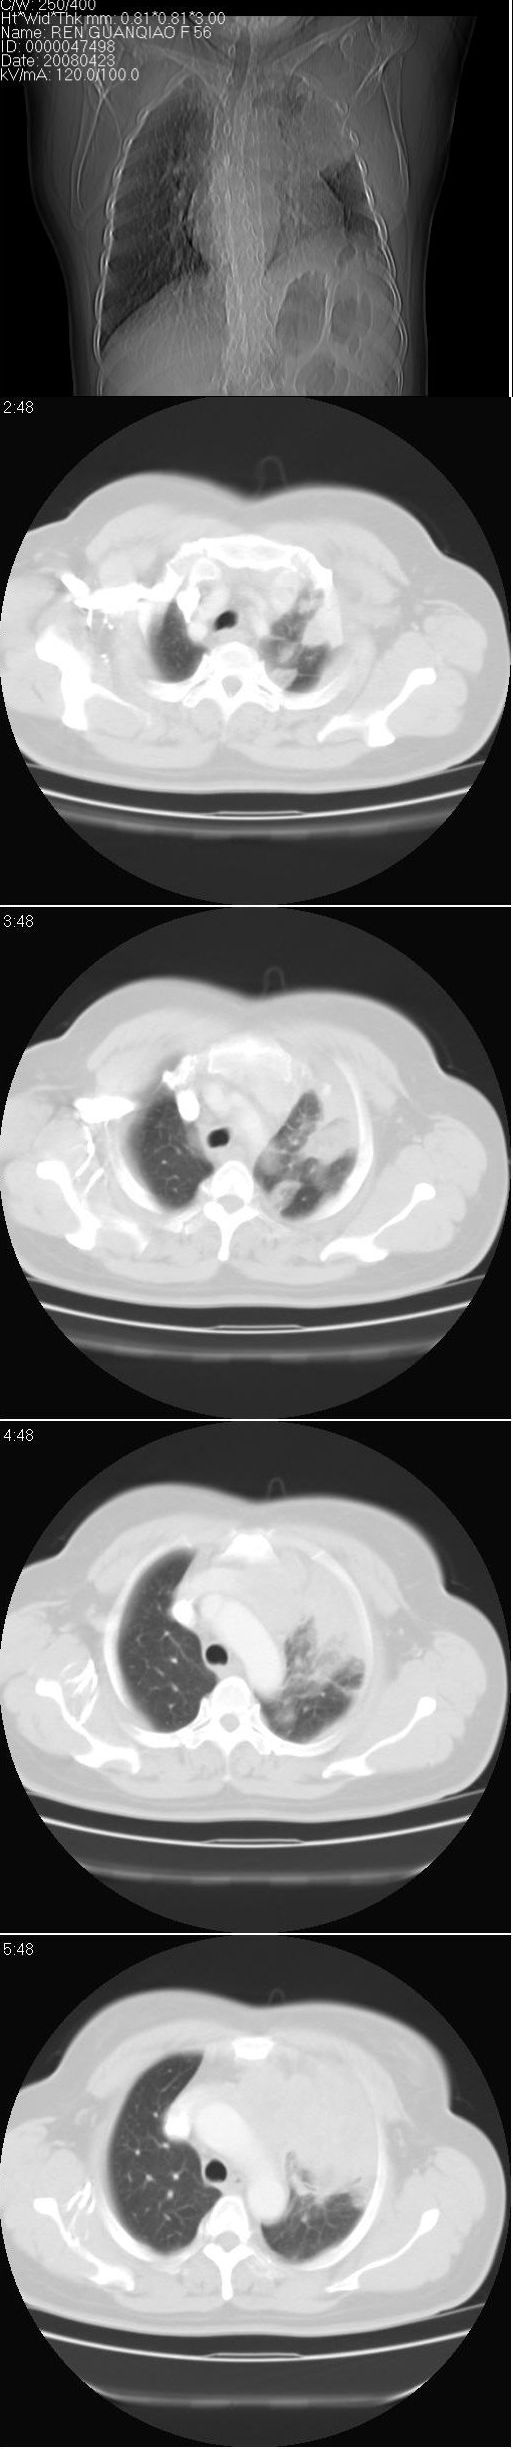

标题: CT13028:女,56岁。咳嗽、气促一月,咳血一周。CT值增加约30 [打印本页]

标题: CT13028:女,56岁。咳嗽、气促一月,咳血一周。CT值增加约30

左上肺肿块伴阻塞性改变,考虑肺癌可能大

感觉病灶主要来源于前上纵隔,向周围浸润,考虑为侵袭性胸腺瘤。

考虑左上肺癌(周围型)伴左肺门及纵隔转移(主肺动脉窗旁病灶可能为肿大并坏死的淋巴结),不除外纵隔型肺癌

软组织肿块,应该有肺不张(因为左膈及脾脏\\胃抬高明显):考虑中央ca

1)考虑为:左肺上叶中心型肺癌伴左肺上叶阻塞性肺炎、节段性肺不张,左肺门及纵隔淋巴结转移。2)左侧少量胸腔积液。